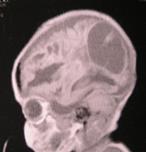

Рис.38. КТ-граммы ребенка с гидроцефалией тяжелой степени, ЛКИ=53%,

после операции нормализация внутричерепных взаимоотношений, ЛКИ= 3,2%.